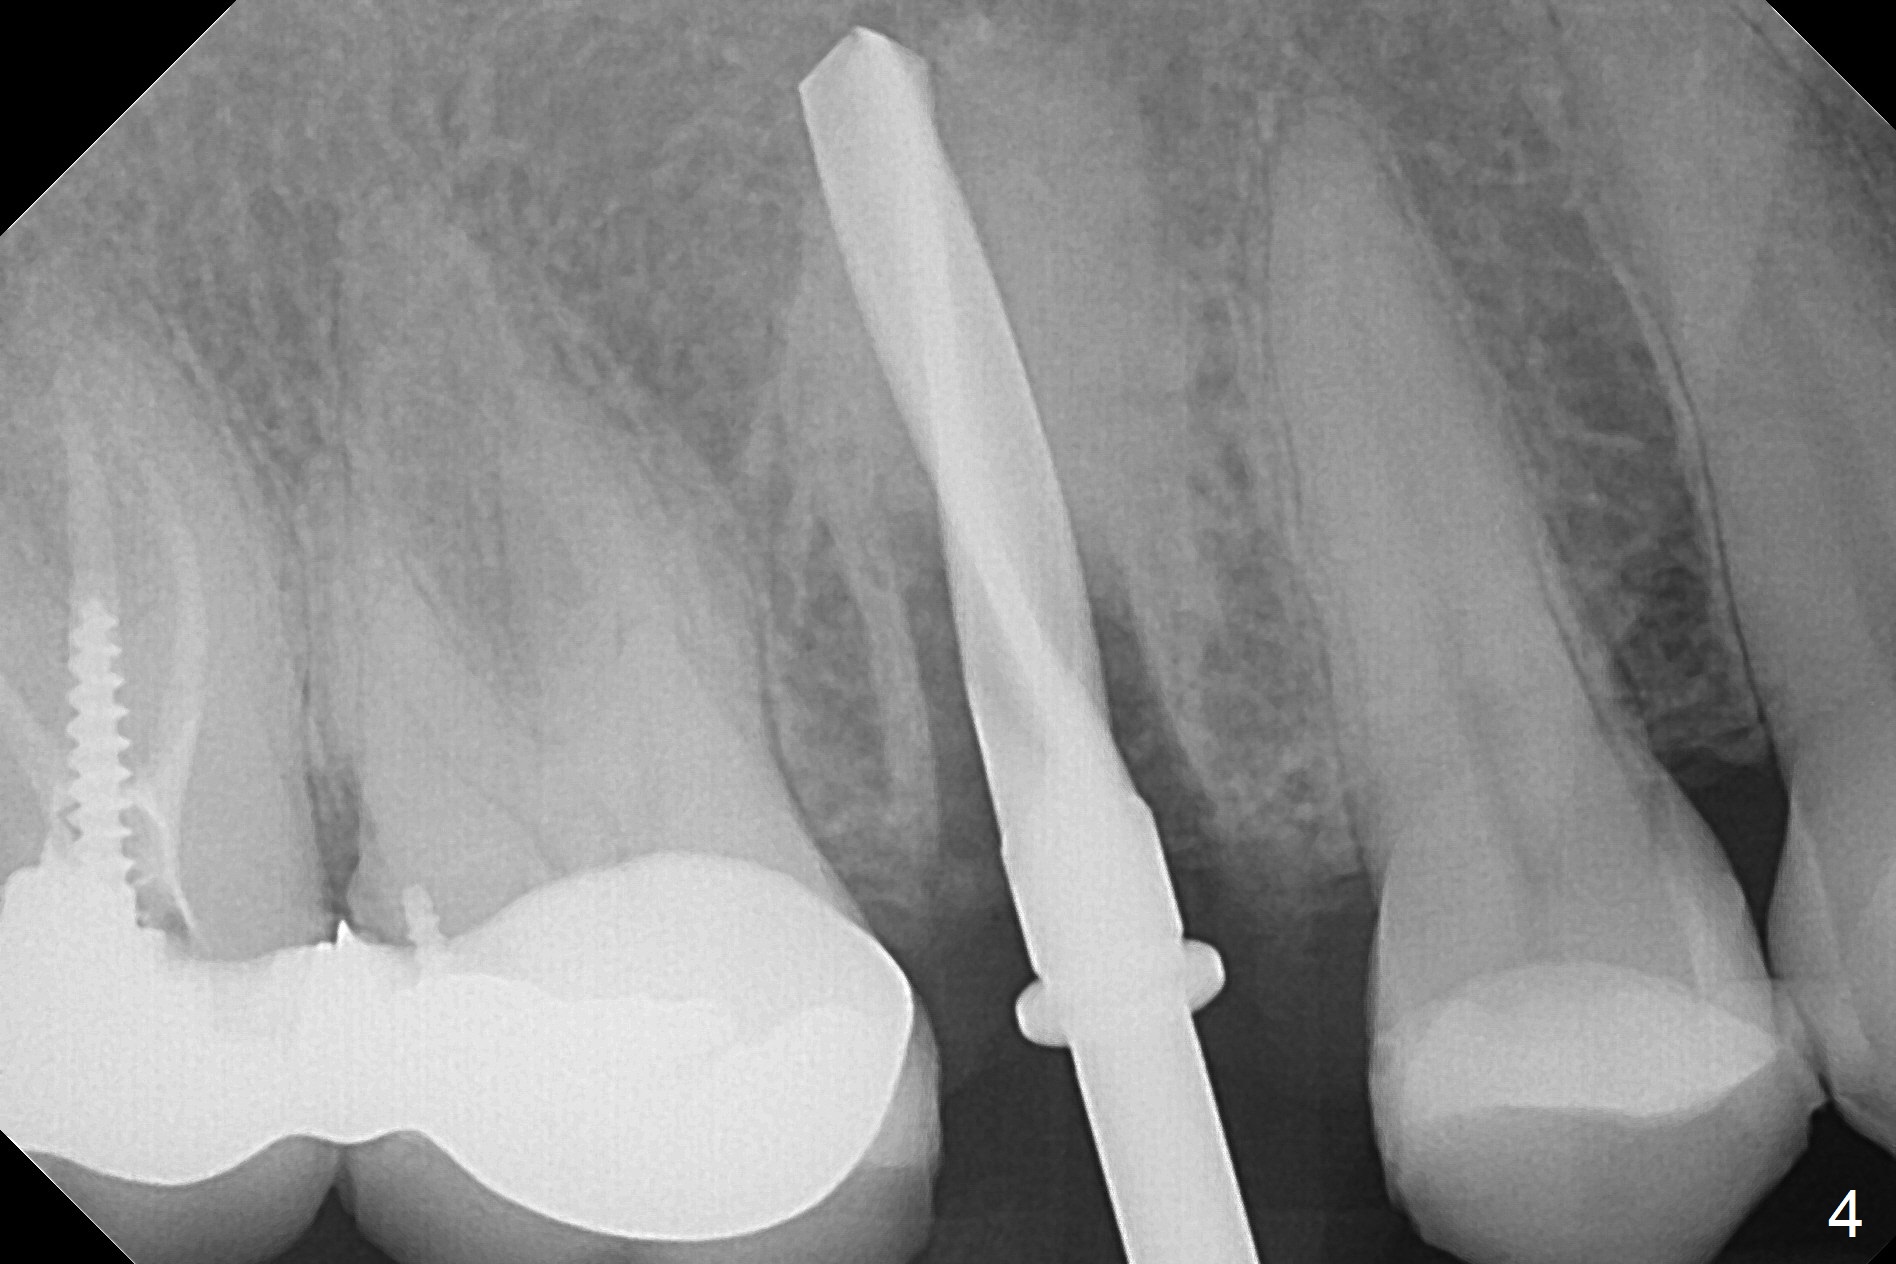

After extraction of the tooth #4 with palatally subgingival fracture (Fig.1 ^), white hard tissue is found in the socket, the density of which is hard (Fig.2 D). When osteotomy passes this portion of the bone (Fig.3 red dashed line), bone density feels reduced suddenly. The osteotomy is moved mesially slightly (Fig.4 (2.7 mm drill)). When a 3.8x15 mm dummy implant is placed with stability, there is an apical space (Fig.5 red dashed line). Therefore the final implant is longer (3.8x18 mm, <30 Ncm, Fig.6, 7). Vanilla graft is placed around the implant and a 4.5x4(4) mm abutment is placed immediately for an immediate provisional (Fig.8). Although the provisional easily dislodges in spite of remake, the implant seems osteointegrated with decreased space 4 months postop (Fig.9). The gingiva is healthy, although it covers the abutment margin partially. Gingivectomy appears necessary for impression.